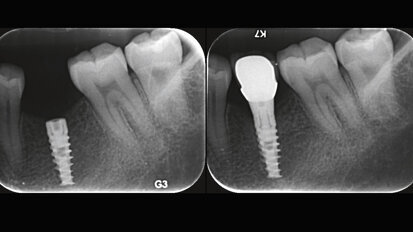

How to give a second life to third molars: A case series with follow-up

Dental autotransplantation entails extracting and repositioning a tooth into a different site in the mouth of the same patient. A successfully transplanted ...